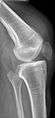

| An x-ray demonstrating quadriceps tendon rupture. Note the abnormal angle of the patella and soft-tissue swelling marked by the arrow. | |

Quadriceps tendon rupture in plain X-ray

Quadriceps tendon rupture in plain X-ray: Incomplete rupture with haematoma in tendon.

X-ray of a tear of the patellar tendon. On the left: The kneecap is pulled up. On the right: Significant dent in the soft tissue above the kneecap.